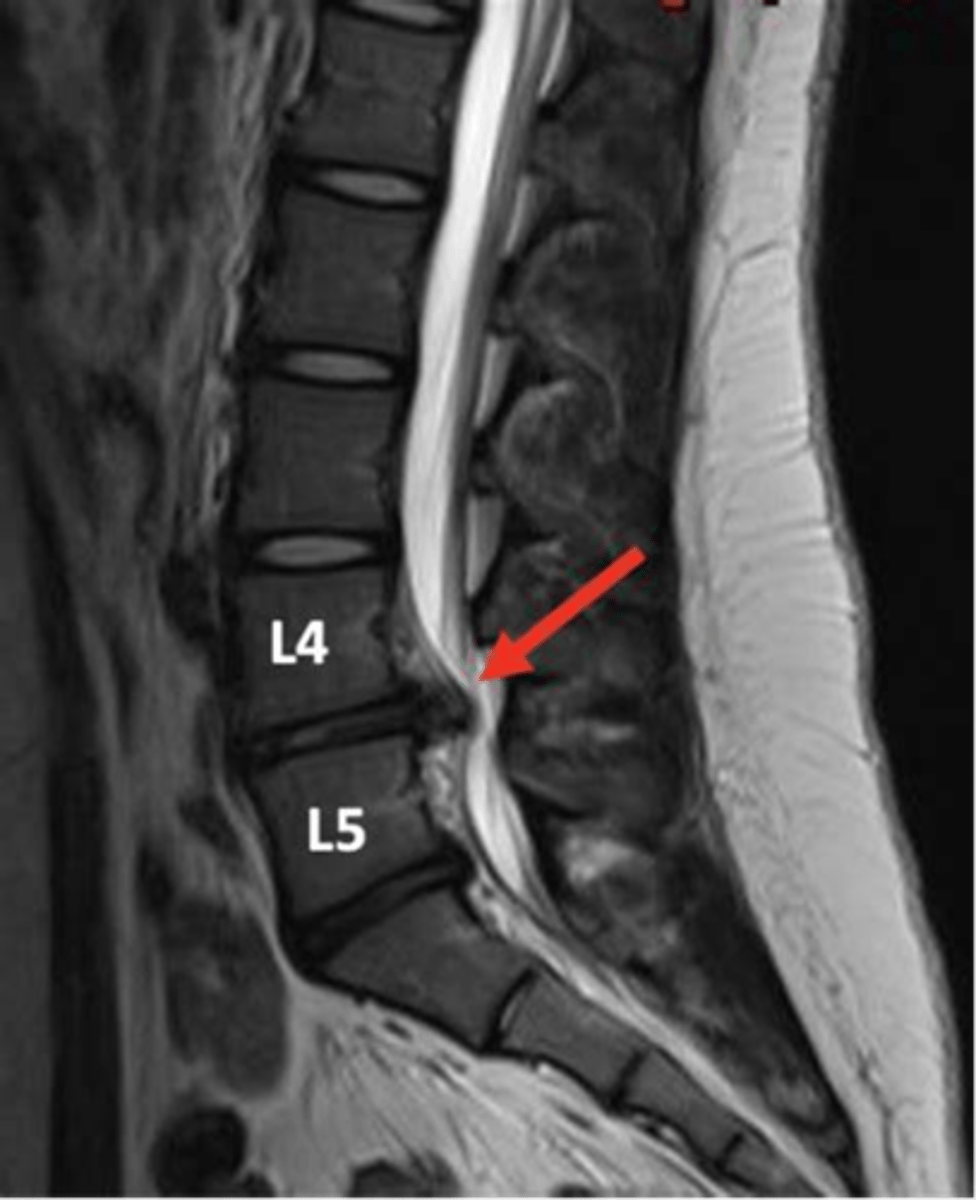

spinal stenosis

Narrowing of the spinal canal that causes pressure on the spinal cord (nerves)

spinal stenosis etiology

osteophytes, disc herniation, tumors, trauma

what are the s/s of spinal stenosis

mild-severe pain, paresthesia, and muscle weakness

cauda equina syndrome is a form of _____ where all nerves in the lower spine are compressed

s/s of cauda equina syndrome

low back pain, radiculopathy, lower extremity weakness, reduced, incontinence of bowel/bladder